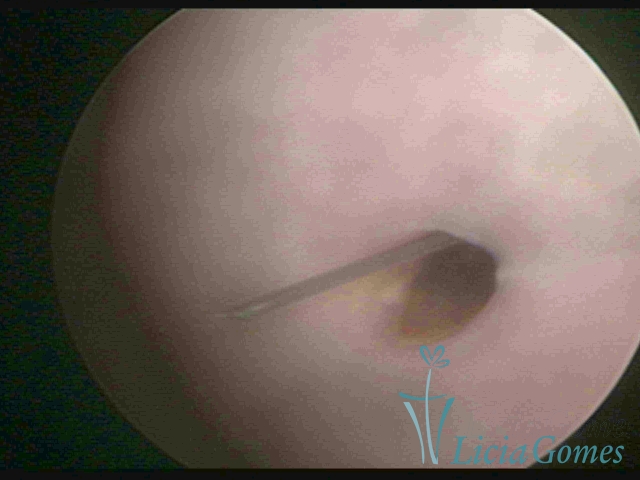

IUD distal extremity

×